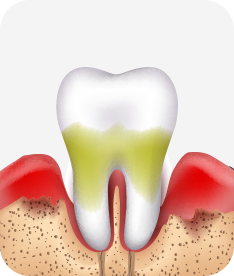

치주염 단계별 증상

치주염 (중기~말기)

주기적으로 잇몸이 붓고 피가 나며, 욱씬하거나 우리한 통증이 나타남.

치주치료 및 정도에 따라 치주수술(잇몸수술)이 필요함. 향후 관리 정도에 따라 3~6개월 간격으로 내원하여 유지치료를 시행하여야 함.